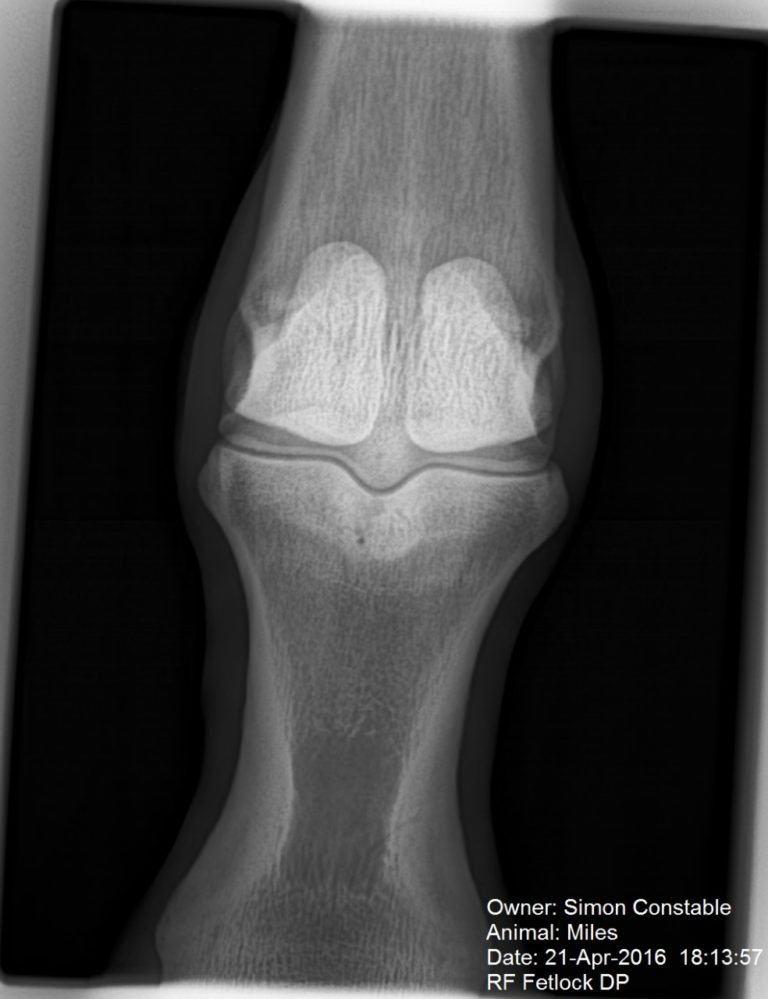

From equine-vets.com

Bone Oedema Talus Bone Oedema The injury may be acute. bone marrow edema (bme) is a descriptive term for a common finding in magnetic resonance imaging (mri). common causes of bone marrow edema in multiple bones in the ankle and foot include high turnover in children,. bone marrow edema can occur due to an injury of a bone or connective tissues like. Talus Bone Oedema.